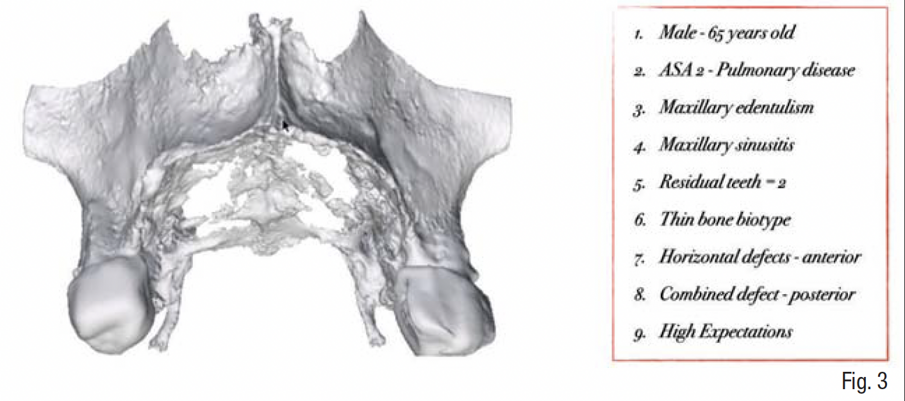

Un paziente di 65 anni, ASA-2, non fumatore è giunto alla nostra osservazione presentando un’edentulia quasi totale del mascellare superiore, con persistenza soltanto dei primi molari 16 e 26 a supporto di una protesi parziale rimovibile, una severa perdita di dimensione verticale occlusale, e una conseguente terza classe acquisita (Fig. 1). La richiesta del paziente era la risoluzione dell’edentulia con protesi fissa supportata da impianti che gli restituisse una funzione e un’estetica ottimale del mascellare superiore ed era già a conoscenza delle problematiche relativa alla mancanza di osso e della necessità di una ricostruzione ossea prima del posizionamento implantare.

Gli esami radiologici di primo livello, quali la OPT, evidenziavano un’altezza ossea sufficiente al posizionamento implantare, ma la successiva analisi di secondo livello, quale la CBCT, evidenziava la presenza di una grave atrofia orizzontale a livello della regione edentula che rendeva impossibile la chirurgia implantare, oltre ad un quadro di sinusite mascellare cronica bilaterale. Su richiesta del paziente, si è deciso di mantenere i 2 molari sup. che sono stati trattati endodonticamente e successivamente protesizzati con 2 corone in zirconia; e di non eseguire il rialzo di seno mascellare bilaterale evitando l’iter terapeutico di approfondimento ORL.

In accordo con il paziente si decide di eseguire un intervento di rigenerazione ossea guidata (GBR) mediante una griglia in titanio customizzata e membrane riassorbibili (Figg. 2-4). Pertanto, 1 mese prima della chirurgia, è stato creato un modello osseo virtuale in formato .stl del mascellare sup. tramite segmentazione, a partire dai file .dicom della CBCT, utilizzando un software biomedicale dedicato (BTK- 3D, Biotec Srl, Dueville, Vicenza, Italy); è stato quindi eseguita la progettazione virtuale dell’aumento di volume osseo necessario per inserire gli impianti e la successiva progettazione della griglia customizzata al di sopra del volume aumentato; infine, è stata realizzata la griglia in titanio vera e propria mediante tecnologia di stampa 3D basata su sinterizzazione laser del titanio (3D-Mesh BTK, Biotec Srl, Dueville, Vicenza, Italy) (Figg. 5-8).